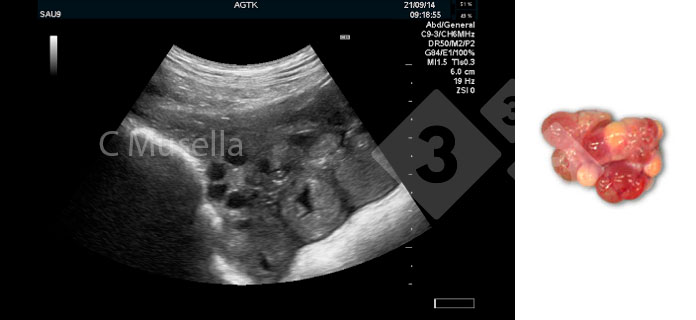

W pobliżu czasu owulacji pęcherzyki przedowulacyjne zmieniają swój kształt z kulistego na jajowaty / wielokątny. Proces owulacji może trwać kilka godzin, a pęcherzyki przedowulacyjne można zaobserwować w połączeniu z ciałkami krwotocznymi; te ostatnie są wyraźnie rozpoznawalne dzięki ich aspektowi echogenicznemu. Owulację uznaje się za zakończoną, jeśli kolejne badania ultrasonograficzne wykazują zniknięcie wszystkich pęcherzyków przedowulacyjnych lub znaczne zmniejszenie liczby wcześniej obserwowanych pęcherzyków przedowulacyjnych.